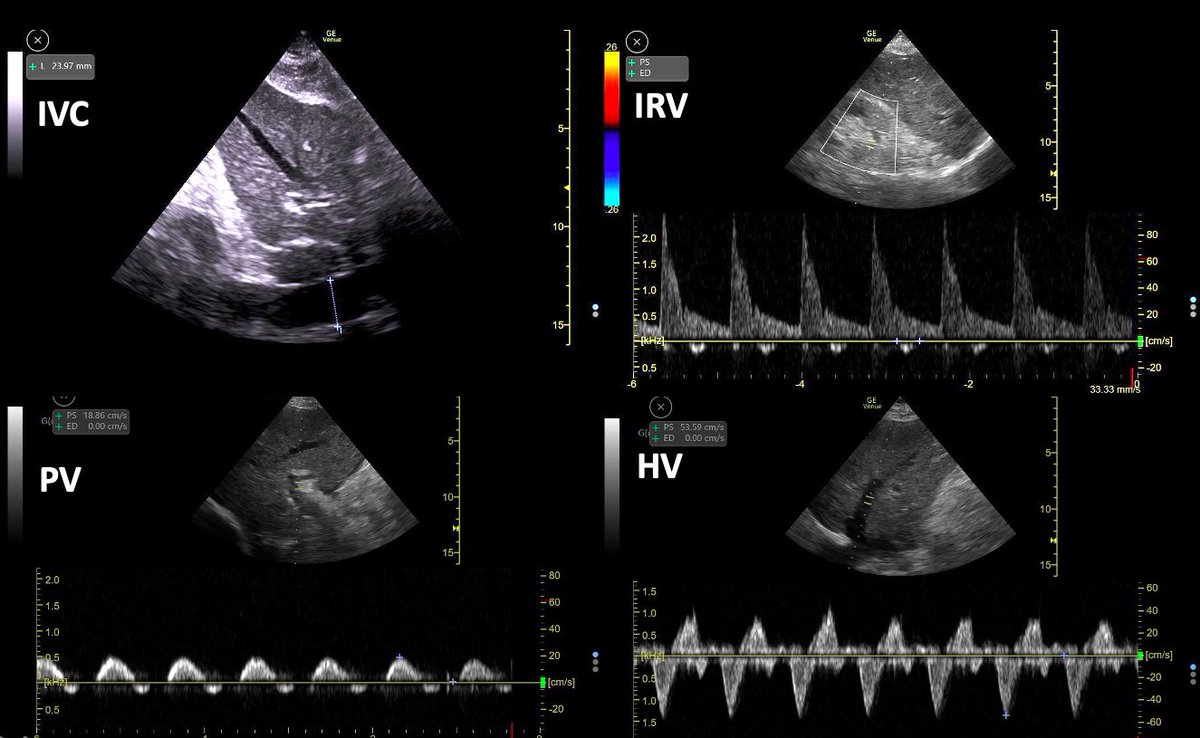

Another one for the AKI Consult series 🧵: 👵 w group 4 Pulmonary Hypertension. Recently 🏥 w severe congestion and AKI 2/2 cardiorenal syndrome with a Cr of 3.5 mg/dl. (Baseline Cr 0.5 mg/dl) After ultrafiltration and IV diuretics the pt was decongested and AKI resolved.. 1/11